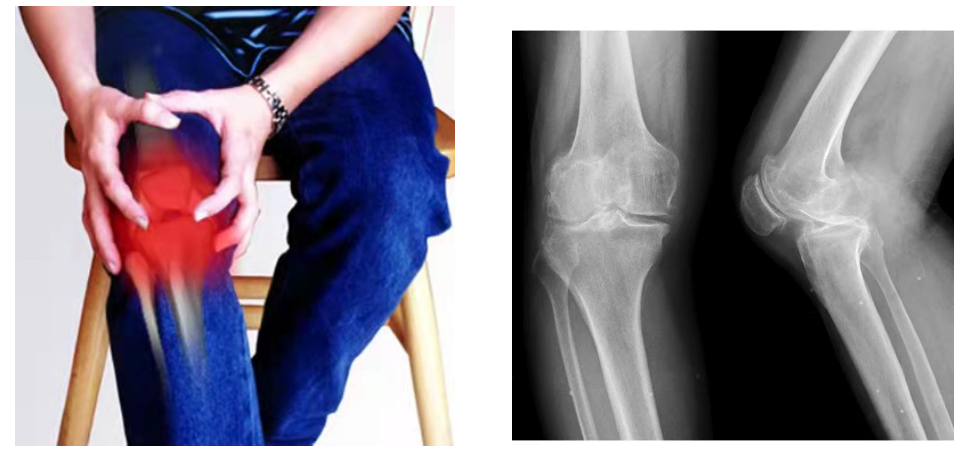

骨性关节炎

骨性关节炎,在民间也被称为“长骨刺”、“骨质增生”,主要是膝关节过劳、长期处于寒湿状态引起膝关节病变。主要表现为⑴疼痛,痛症为:①起步痛,久坐或刚下床行走时疼痛明显,活动后可缓解;②负重、上下楼梯时疼痛加重;③静息状态也会疼痛,夜间更痛。⑵活动受限,晨僵,即早上起床时自觉关节僵硬,一般持续时间小于30分钟。⑶关节畸形、肿大,早期可见肿胀,中晚期出现畸形。⑷关节屈伸时有骨擦感。